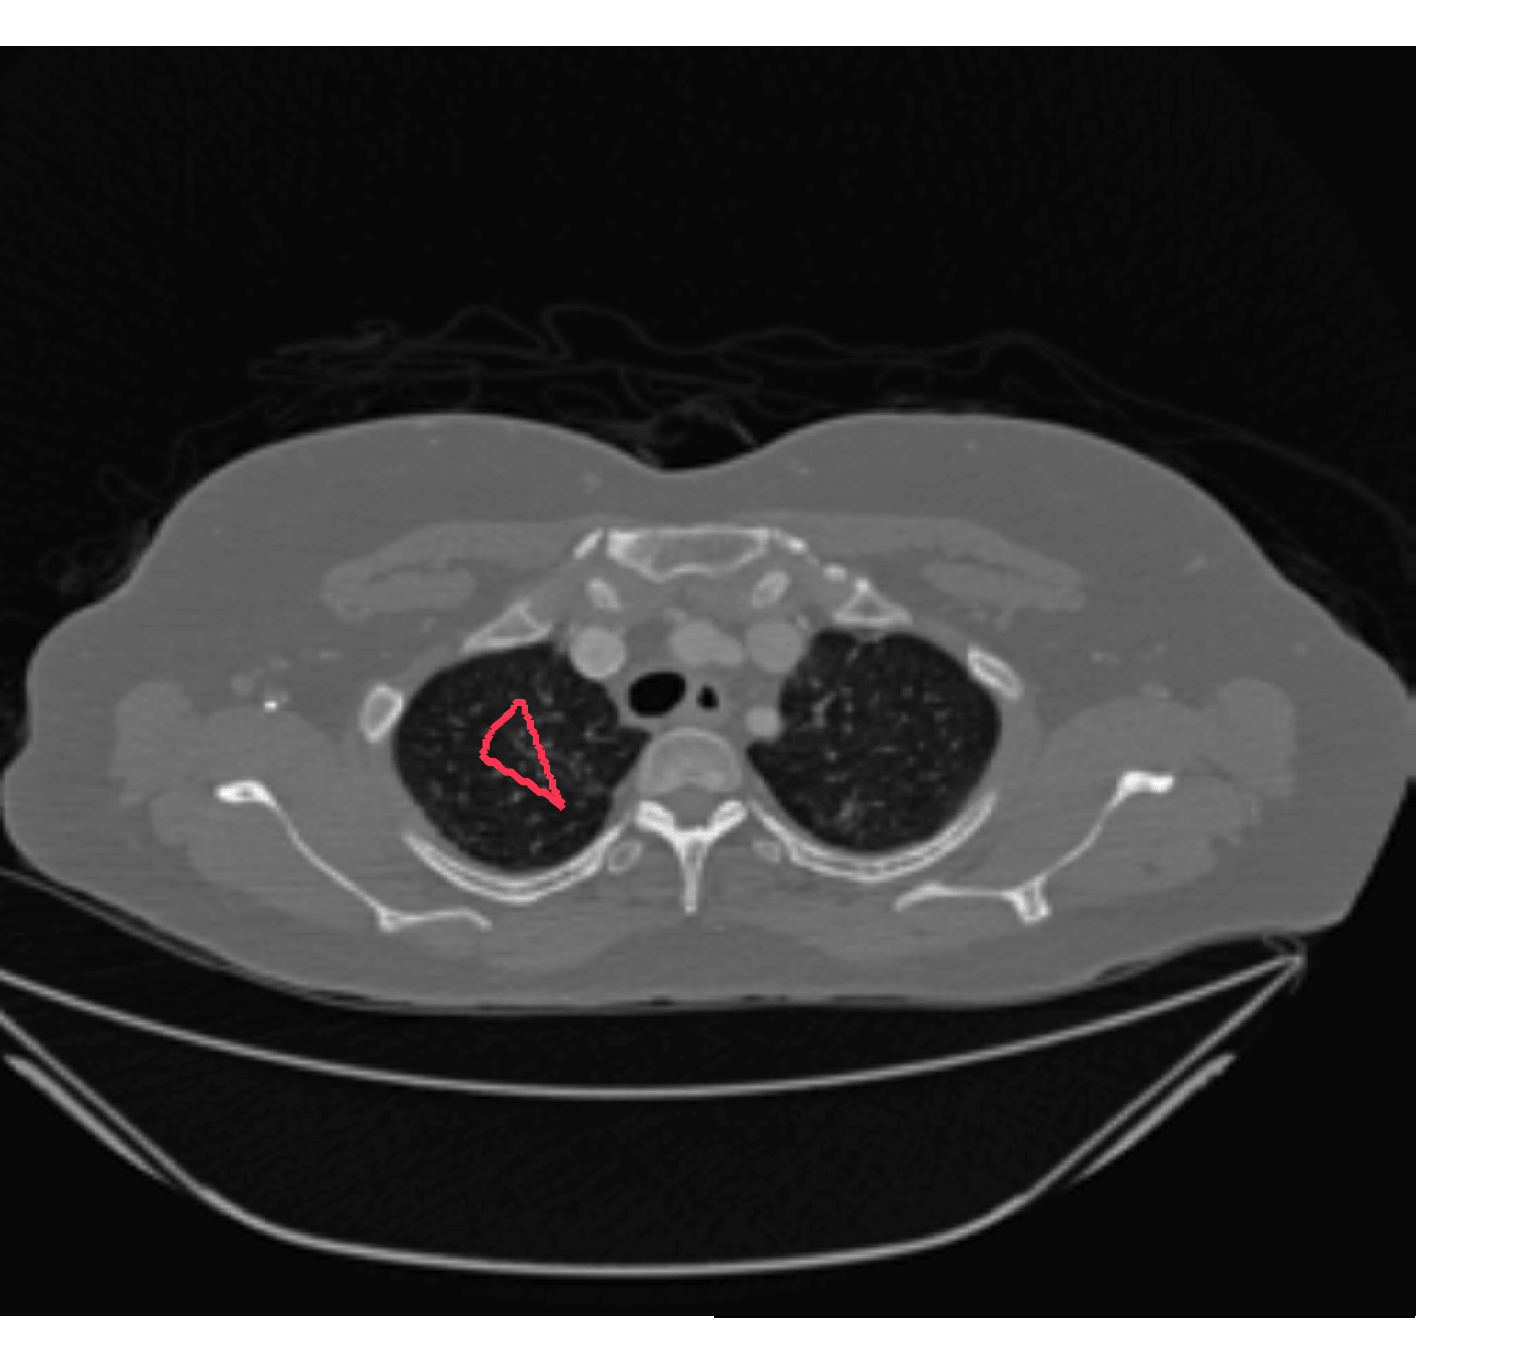

The motivation for this work comes from observing contradictions in using piecewise-constant intensity fitting terms in selective segmentation. Whilst good results are possible with this approach, the exceptional cases lead to severe limitations in practice. This is quite common in medical imaging as demonstrated in Fig. 1, where the target foreground has a low intensity. Given that the corresponding background includes large regions of low intensity, the optimal average intensities for this segmentation problem are and . For cases where , we see that by (1), almost everywhere in the domain . This means that it is very difficult to achieve an adequate result, without an over-reliance on the user input or parameter selection.

| (10) |

In this section we introduce the proposed data fitting term for selective segmentation. We consider objects that are approximately homogeneous in the target region. Intrinsically, it is then assumed that the region , provided by the user, is likely to provide a reasonable approximation of the optimal value and therefore an appropriate foreground fitting function, , is given by CV (2). For this reason, it makes sense to retain this term in the proposed approach. The contradiction is in how the background fitting function is defined. Considering piecewise-constant assumptions of the image, and many of the related approaches, the background is expected to be defined by a single constant value, . If then everywhere, and therefore the fitting term can’t accurately separate background regions from the foreground. It is not practical to rely on to overcome this difficulty as it will produce an over-dependence on the choice of and . This is prohibitive in practice. An alternative function must therefore be defined which is compatible with and . Here, we define a new data fitting term that penalises background objects in such a way that avoids these problems by allowing intensity variation above and below the value . In order to design a new functional, we first look at the original CV background fitting function

We define the proposed data fitting functional as follows:

for and as defined in (33). This is consistent with respect to the intensities of the observed object and the concept of selective segmentation. In Fig. 3 we see the difference between CV and the proposed fitting terms for given user input on a CT image. For the CT image, the CV fitting terms are near 0 within the target region. This is despite there being a distinct homogeneous area with good contrast on the boundary. This illustrates the problem we are aiming to overcome. With the proposed fitting term this phenomenon should be avoided in cases like this. By defining as in (33) there is no contradiction if the foreground and background intensities of the target region are similar.